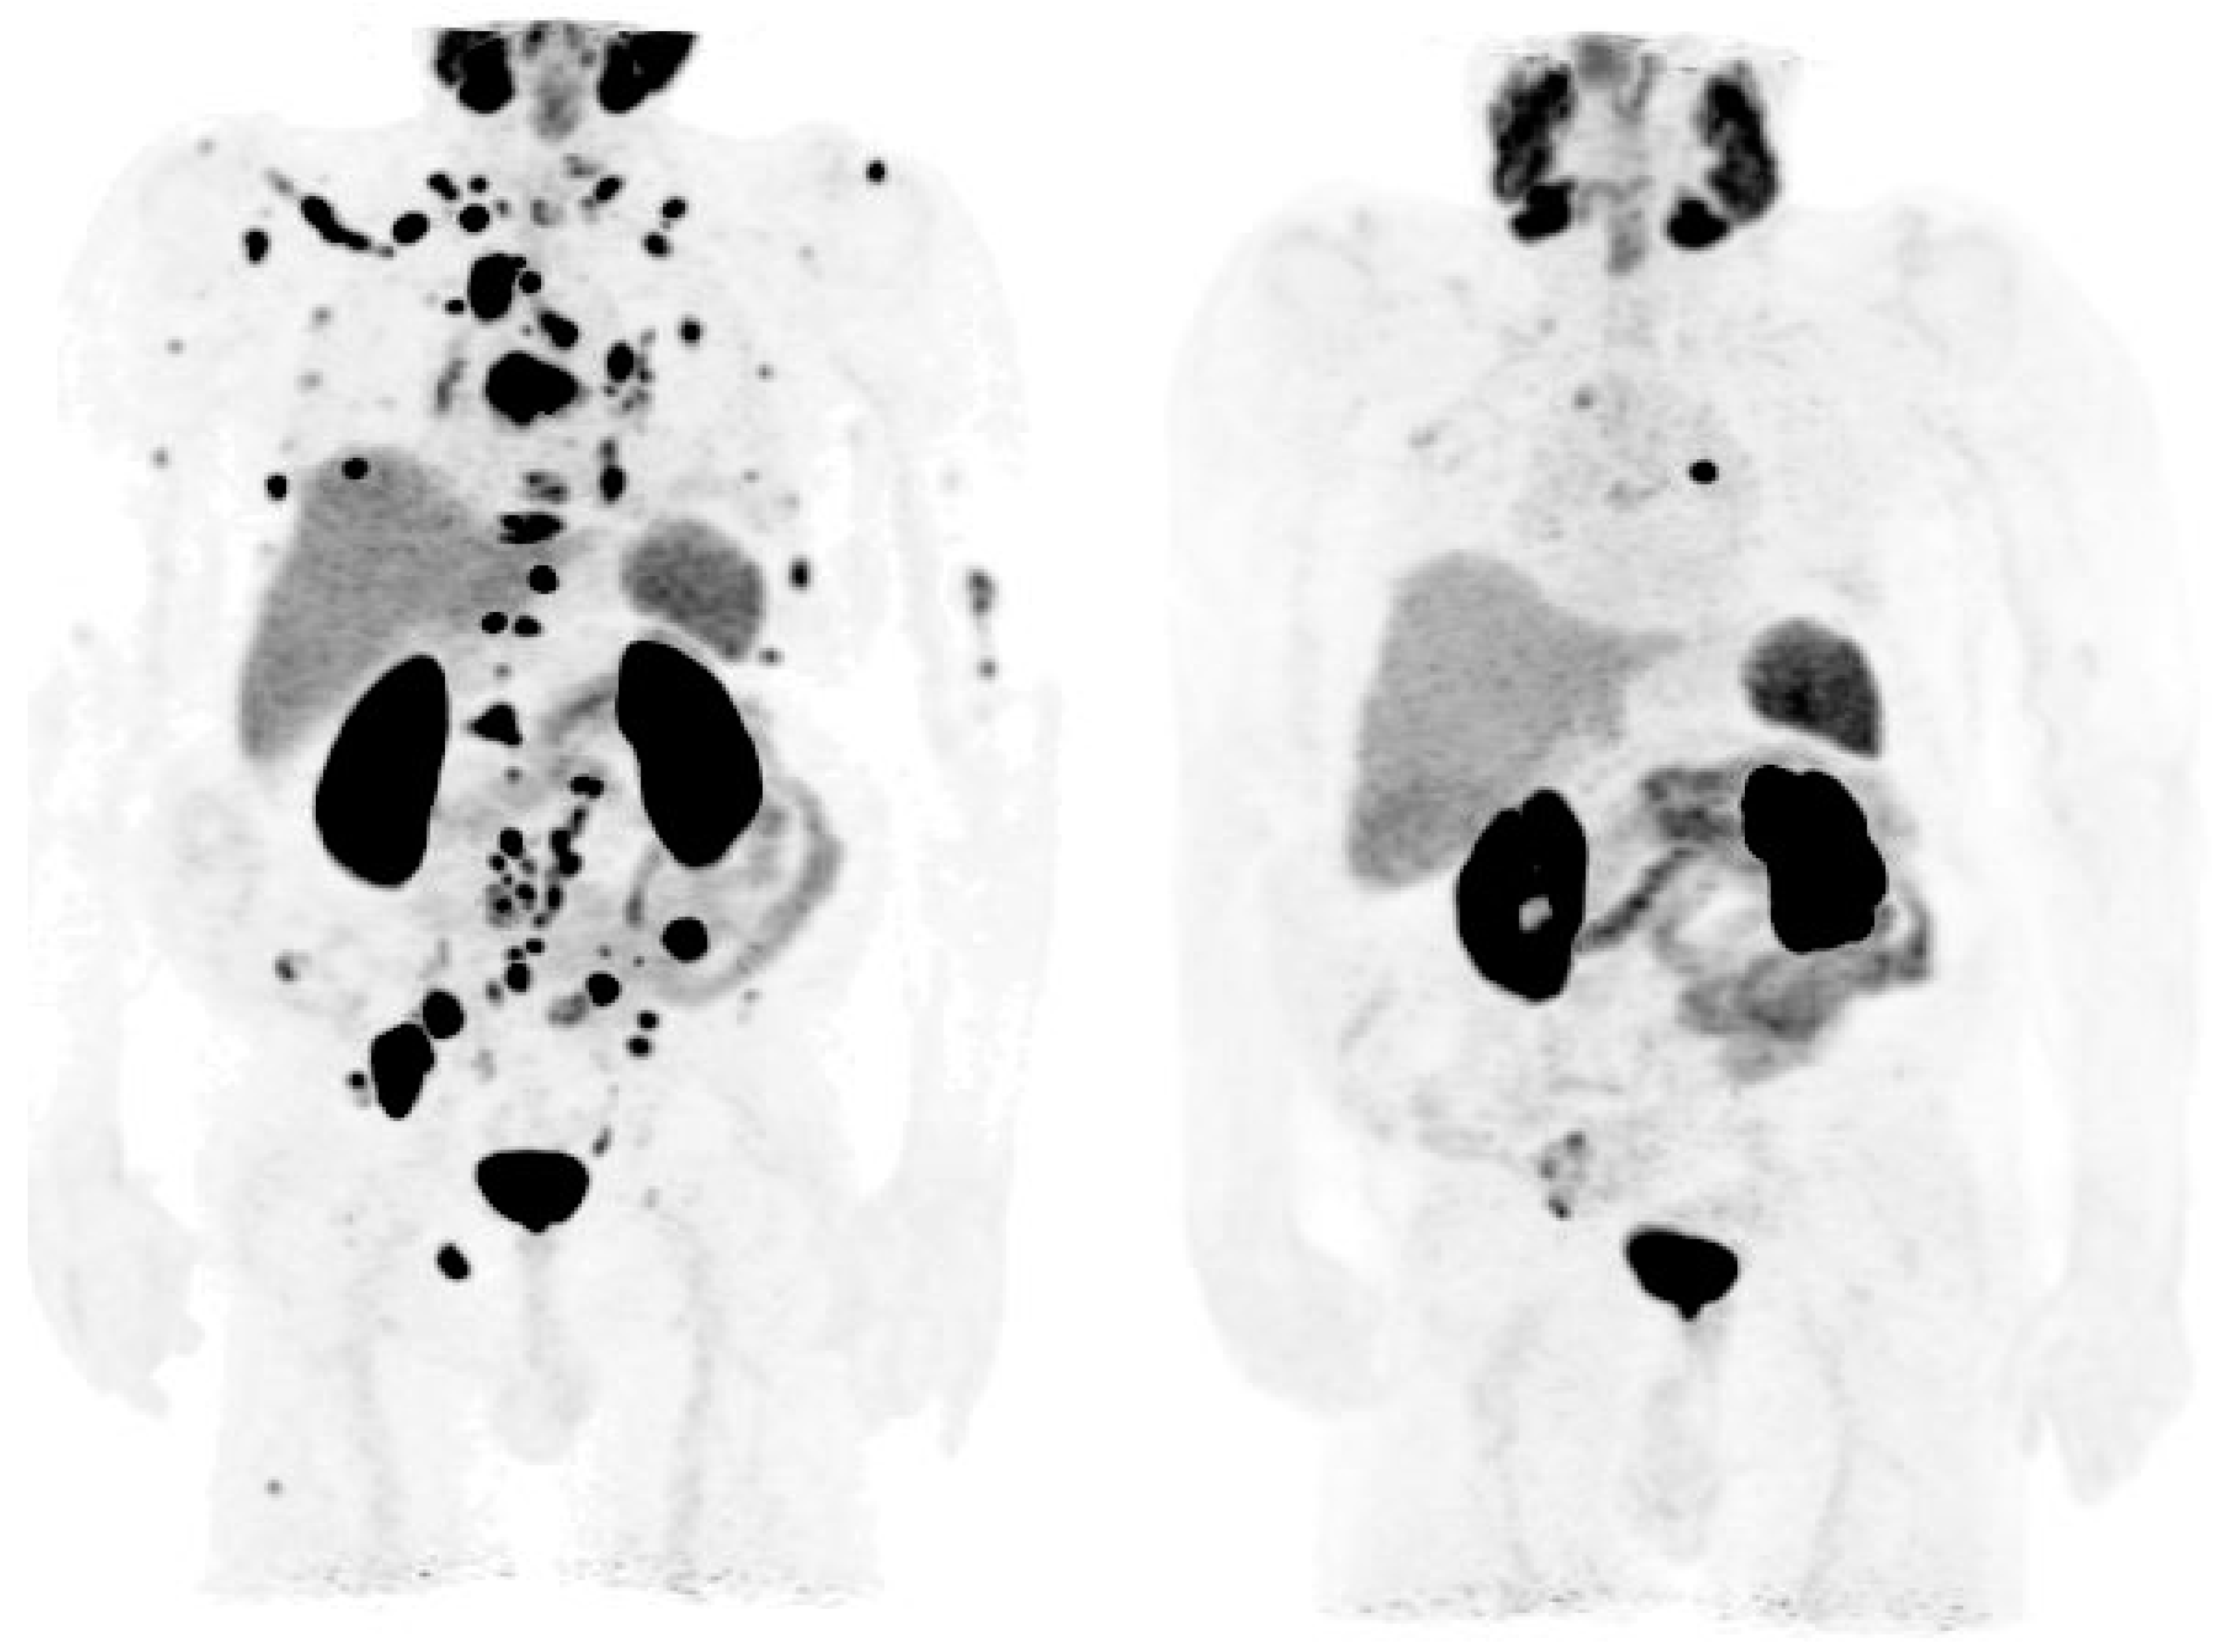

3.2. PSMA PET in Biochemical Recurrence PCa

3.3. Evaluation of PCa Patients for Possibility of PSMA Radioligand Therapies